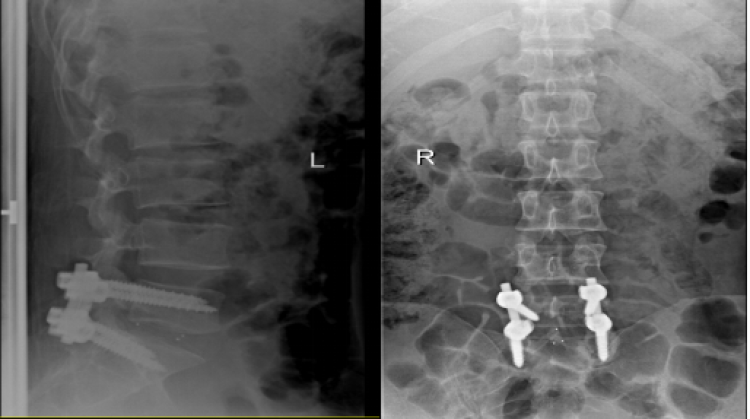

骨科何博主任、刘春主任带领手术团队周末加班为方先生行“腰椎间盘突出髓核摘除,cage植入,椎弓根螺钉固定术”。

△术前影像图

△术后影像图